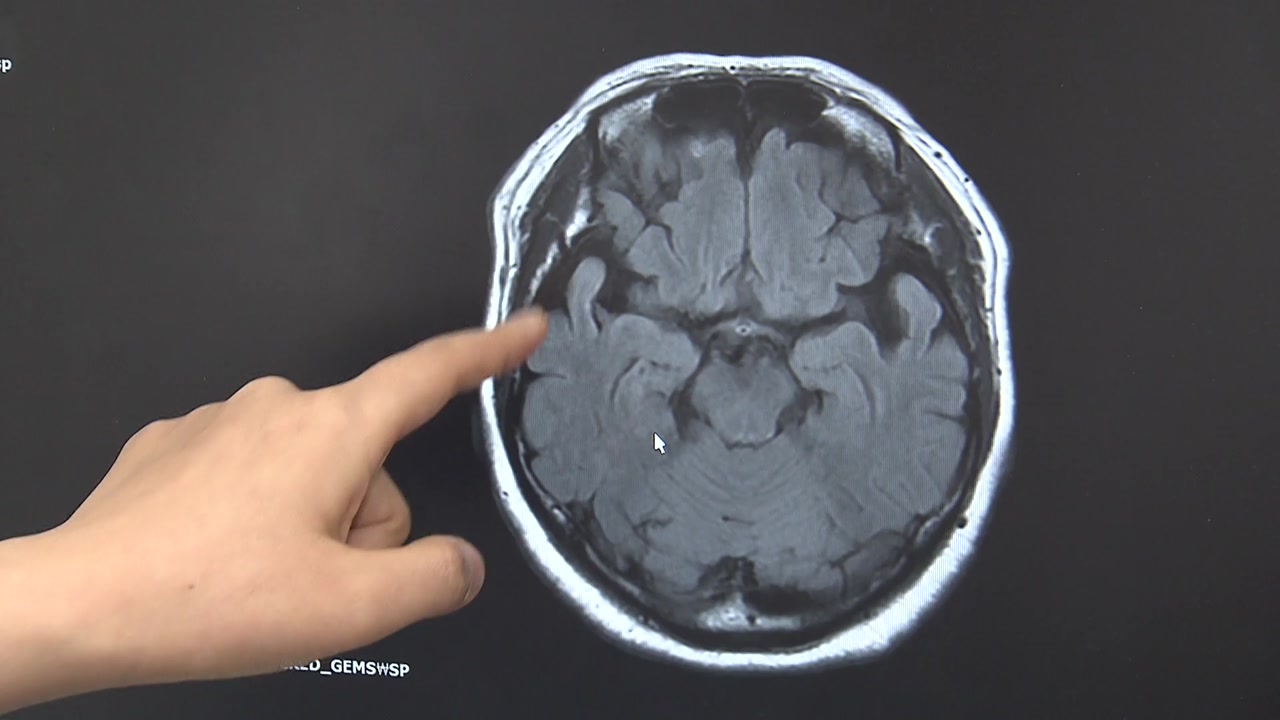

코에 있는 후각신경은 뇌에서 감정과 기억을 담당하는 변연계와 연결돼 있습니다.

특히 기억 중추인 해마가 변연계에 있는 점이 후각 저하와 '브레인포그' 사이의 연관성에 근거가 되고 있습니다.

[정영희 / 명지병원 신경과 교수 : 후각이 후각 상피세포에서 후각신경을 지나서 뇌 변연계, 해마가 기억의 센터이거든요, 그런 쪽으로 이제 해부학적으로 기능 적으로 연결되어 있기 때문에 연관이 있을 수 있지 않나 생각하고 있습니다.]